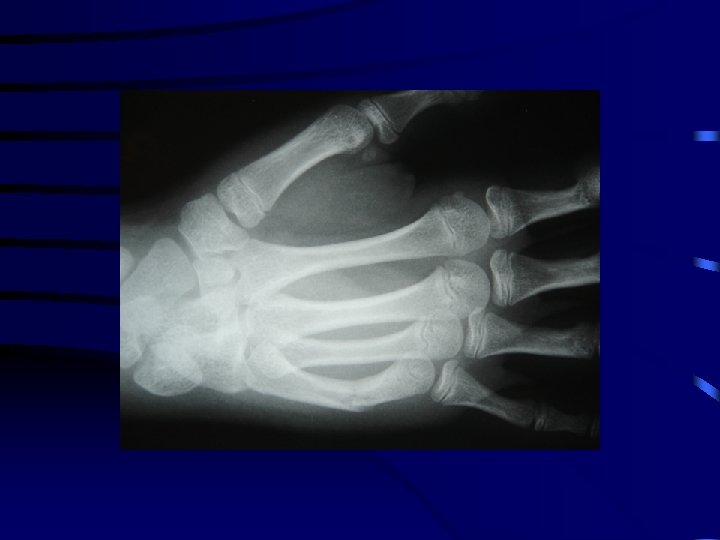

4 La fracture plastique • L'os présente une déformation sans trait de fracture. • L'exemple le plus fréquent est la fracture plastique de l'ulna (cubitus) associée à une luxation de la tête radiale. .

La fracture plastique